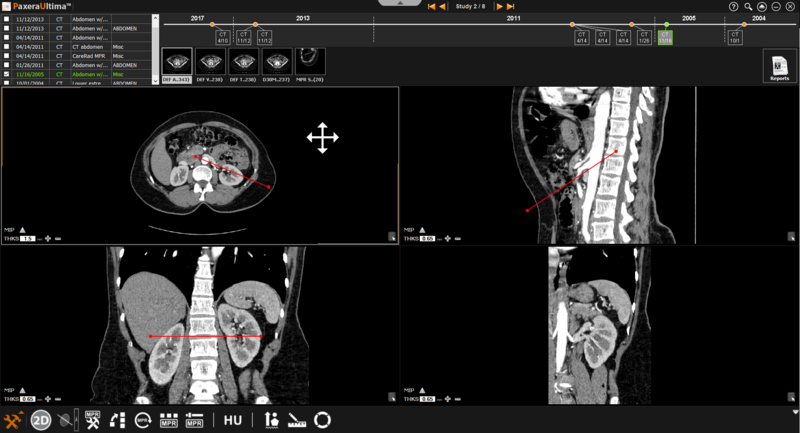

9.4.4. Oblique Mode

The oblique mode is similar to the bioblique mode as the user can adjust the angle of the plane. However, you can only manipulate one plane at a time.

» Adjust line position - The positions of the lines can be adjusted by clicking on the line of interest and dragging it in the direction of interest.

» Adjust line angle - The angle of the lines can be adjusted by clicking on the circle at the end of the line and dragging it in the direction of interest.